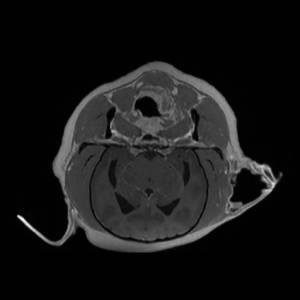

Main Gallery

Playing with a photo gallery function. It is possible to have multiple galleries, each within a namespace.